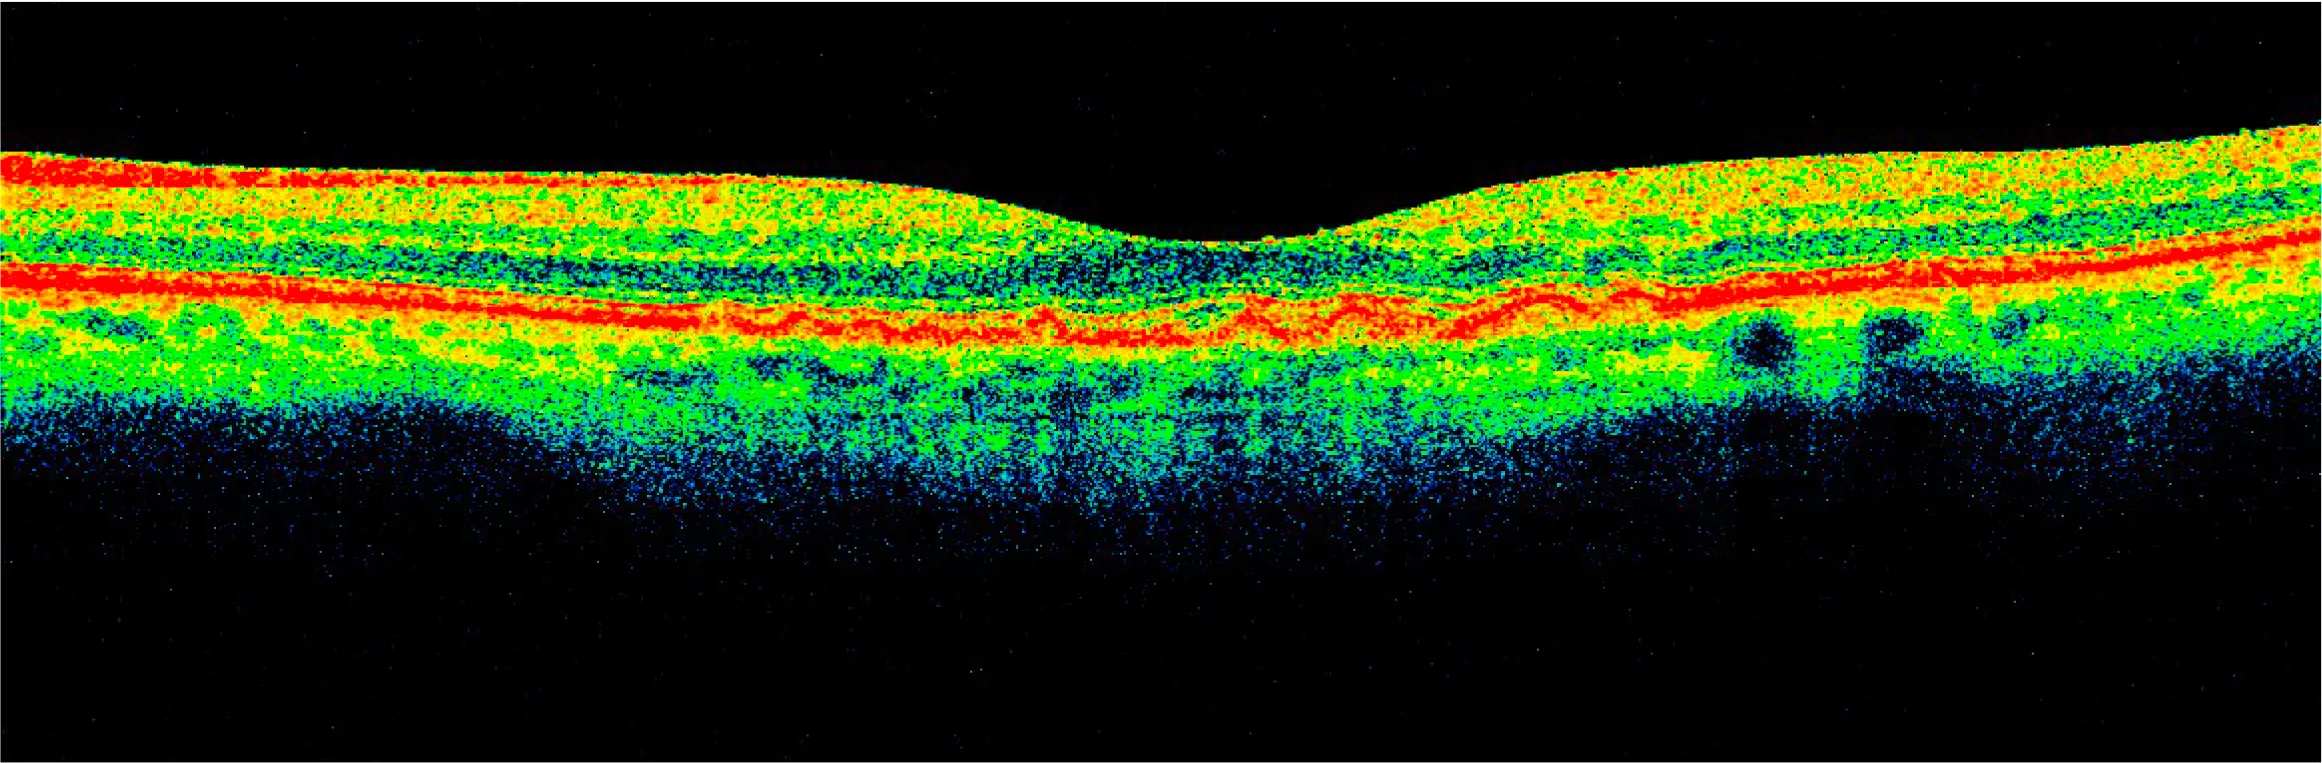

At her 6-month follow-up, her drusen were decreased by about 70%.

It inspired me to use AI to turn the OCT scans into a video to help visualize the healing process...

After years of deterioration on AREDS2 and other more conventional nutritional supplements, drusen largely resorbed in 15 months on a higher priced broad spectrum botanical/nutritional regimen, restoring 20/20 visual acuity in each eye as well as distortion-free Amsler Grids.